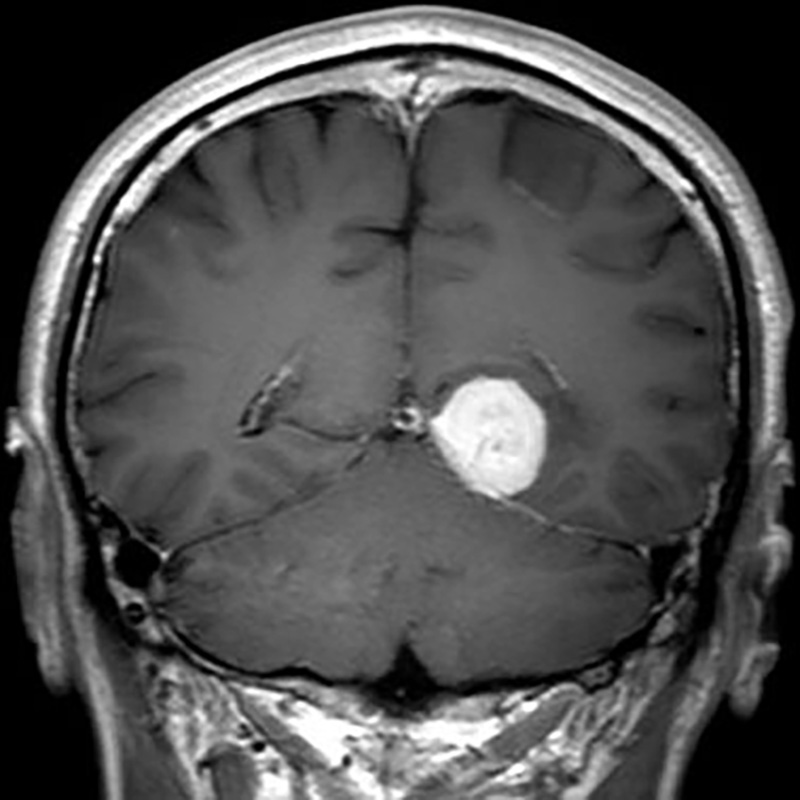

No.’22_12 手術前1

No.’22_12 手術前2